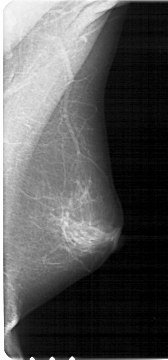

A_1373_1.RIGHT_MLO

RIGHT_MLO LINES 5386 PIXELS_PER_LINE 2506 BITS_PER_PIXEL 12 RESOLUTION 43.5 NON_OVERLAY